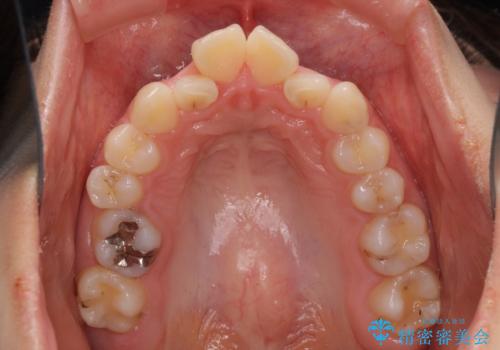

デコボコで飛び出した前歯 ワイヤー装置による抜歯矯正

- 上下前歯のデコボコと、飛び出した前歯を気にして来院された患者様です。

口元を積極的に引っ込めるために、上下左右の小臼歯計4本を抜歯することとしました。

咬み合わせが深く、咬合力強いため、補助装置を使用しながら積極的に口元を下げることとしました。